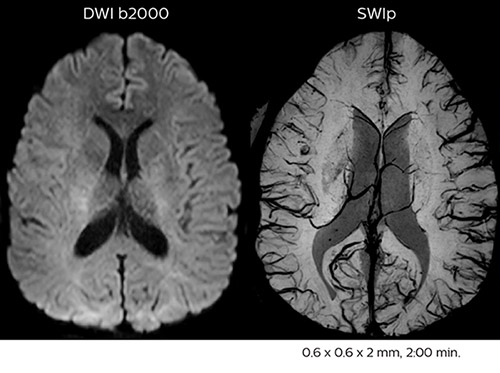

Dr. Savatovsky appreciates the improvements and flexibility that Elition with Compressed SENSE and MultiBand SENSE provides, particularly for stroke patients. “For stroke, it allows us to cut about 5 minutes off of our stroke protocol, or to keep the same acquisition time and get more insights.” The ability to perform more sequences can help in making a swift and confident diagnosis. “For example, our stroke cases usually include the regular sequences that every center does (b1000 diffusion, FLAIR, time-of-flight angiography), but we also image supra aortic vessels, and we can replace a gradient echo sequence with a fast 50-second susceptibility-weighted sequence, and all of this doesn’t add much time. because all the regular sequences are accelerated on Elition.” “The time savings with Compressed SENSE and MultiBand SENSE make it easier to add sequences to give us additional insights. Depending on the context and the first results, we might add a DSC perfusion to assess the ischemic penumbra, an ASL perfusion to help find an alternative cause in case of normal diffusion, or add a high-resolution T1 sequence for a stroke patient, to quickly assess wall imaging in emergency cases. The additional sequences can help improve patient management, because we can already consider some alternative diagnoses if the morphological MRI is normal.”

Using MultiBand SENSE allowed the staff to improve their diffusion quality. “Our diffusion sequence was already fast before, about 40 seconds. Now with Elition, it still lasts 40 seconds, but we improved the spatial resolution by 0.2 mm and use high b-values to be more sensitive to visualize changes related to acute stroke,” says Dr. Savatovsky. “We now also developed a high resolution DTI sequence (1.3 x 1.3 x 2 mm) that can be reformatted and takes 2 to 5 minutes depending on the coverage. We use it every time we have a doubt, or when we expect the diffusion to be abnormal but don’t see that on the fast sequence. We occasionally spot small ischemic infarctions that would not have been visible with the regular diffusion sequence.”

In this patient with acute right motor deficit and aphasia, the b2000 diffusion weighted image is normal. The SWIp image demonstrates more prominent veins in the right hemisphere, which could reflect increased deoxyhemoglobin contents. Fast ASL shows low CBF regions in the left frontal lobe. A follow-up ASL after one hour demonstrates high CBF values in the same area. The final diagnosis was migraine with aura.